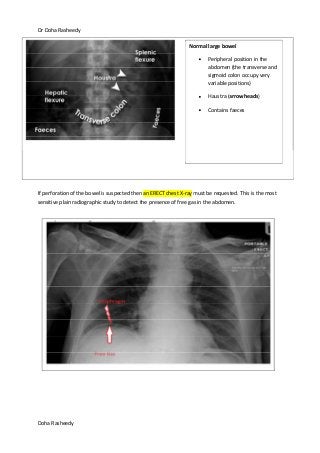

If perforation of the bowel is suspected then an ERECT chest X-ray must be requested. This is the most

sensitive plain radiographic study to detect the presence of free gas in the abdomen.

Normal large bowel

Peripheral position in the

abdomen (the transverse and

sigmoid colon occupy very

variable positions)

Haustra (arrowheads)

Contains faeces